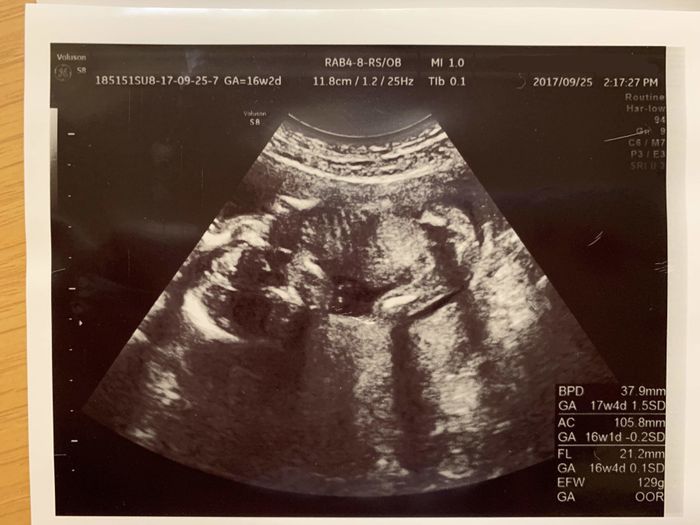

妊娠16週目 おなかの中は少し窮屈なのかな?

妊娠16週目のエコー写真です。安定期と言われる妊娠5ヶ月に入り、戌の日に水天宮へお参りに行きました。そして職場の同僚にも妊娠を報告。さすがに3人目の赤ちゃんは珍しいようで、「おめでとう!」よりも、「え、3人目?」という反応が多かったです。この時のエコーの赤ちゃんは足を屈伸させて両手でのびをしていたので、「もう狭くなってきちゃったかな?」なんて、私は考えていました。